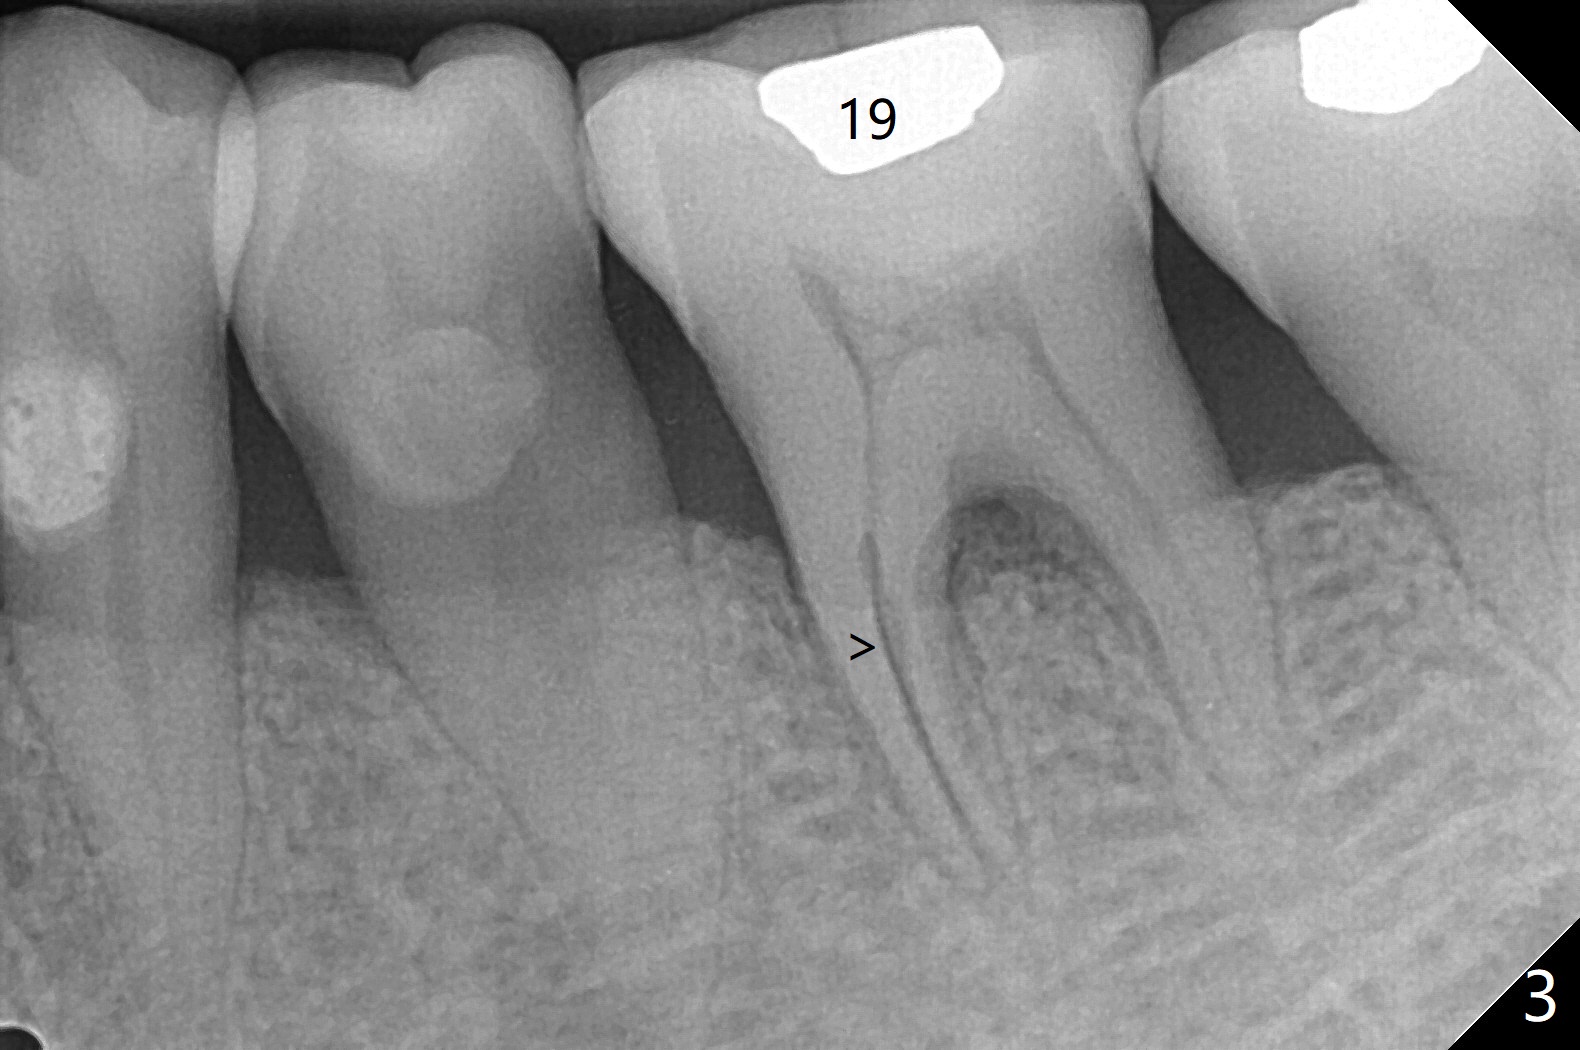

57岁女全口牙龈萎缩骨质吸收,其实卫生好,3号牙金属圈多年,治疗牙齿隐裂,骨质吸收和牙裂与咀嚼力大有关。最近抱怨19,30号牙敏感(图一),涂脱敏剂无效,拍摄根尖片(图二,三),显示30号牙远中根,19号牙近中根从牙槽嵴开始仿佛纵裂(图二,三),牙周探针患根周围触痛。磨牙牙根好像一段式植体,断裂总是发生于牙槽嵴顶,不过是横裂,所以一定要植入牙槽嵴之下,还要考虑今后牙槽嵴吸收。如何确诊牙根纵裂呢?例如19号牙CT显示颊侧近中根(图四,六:B)牙槽嵴处断裂(箭头)。利用一个叫Profile Program(Profilogram)测定近中根横断面平均密度,舌侧密度基本均匀(图七),而颊侧断裂处密度突然降低(图八)。当断裂还不是很明显时(隐裂),测定平均密度就显得重要,帮助诊断。